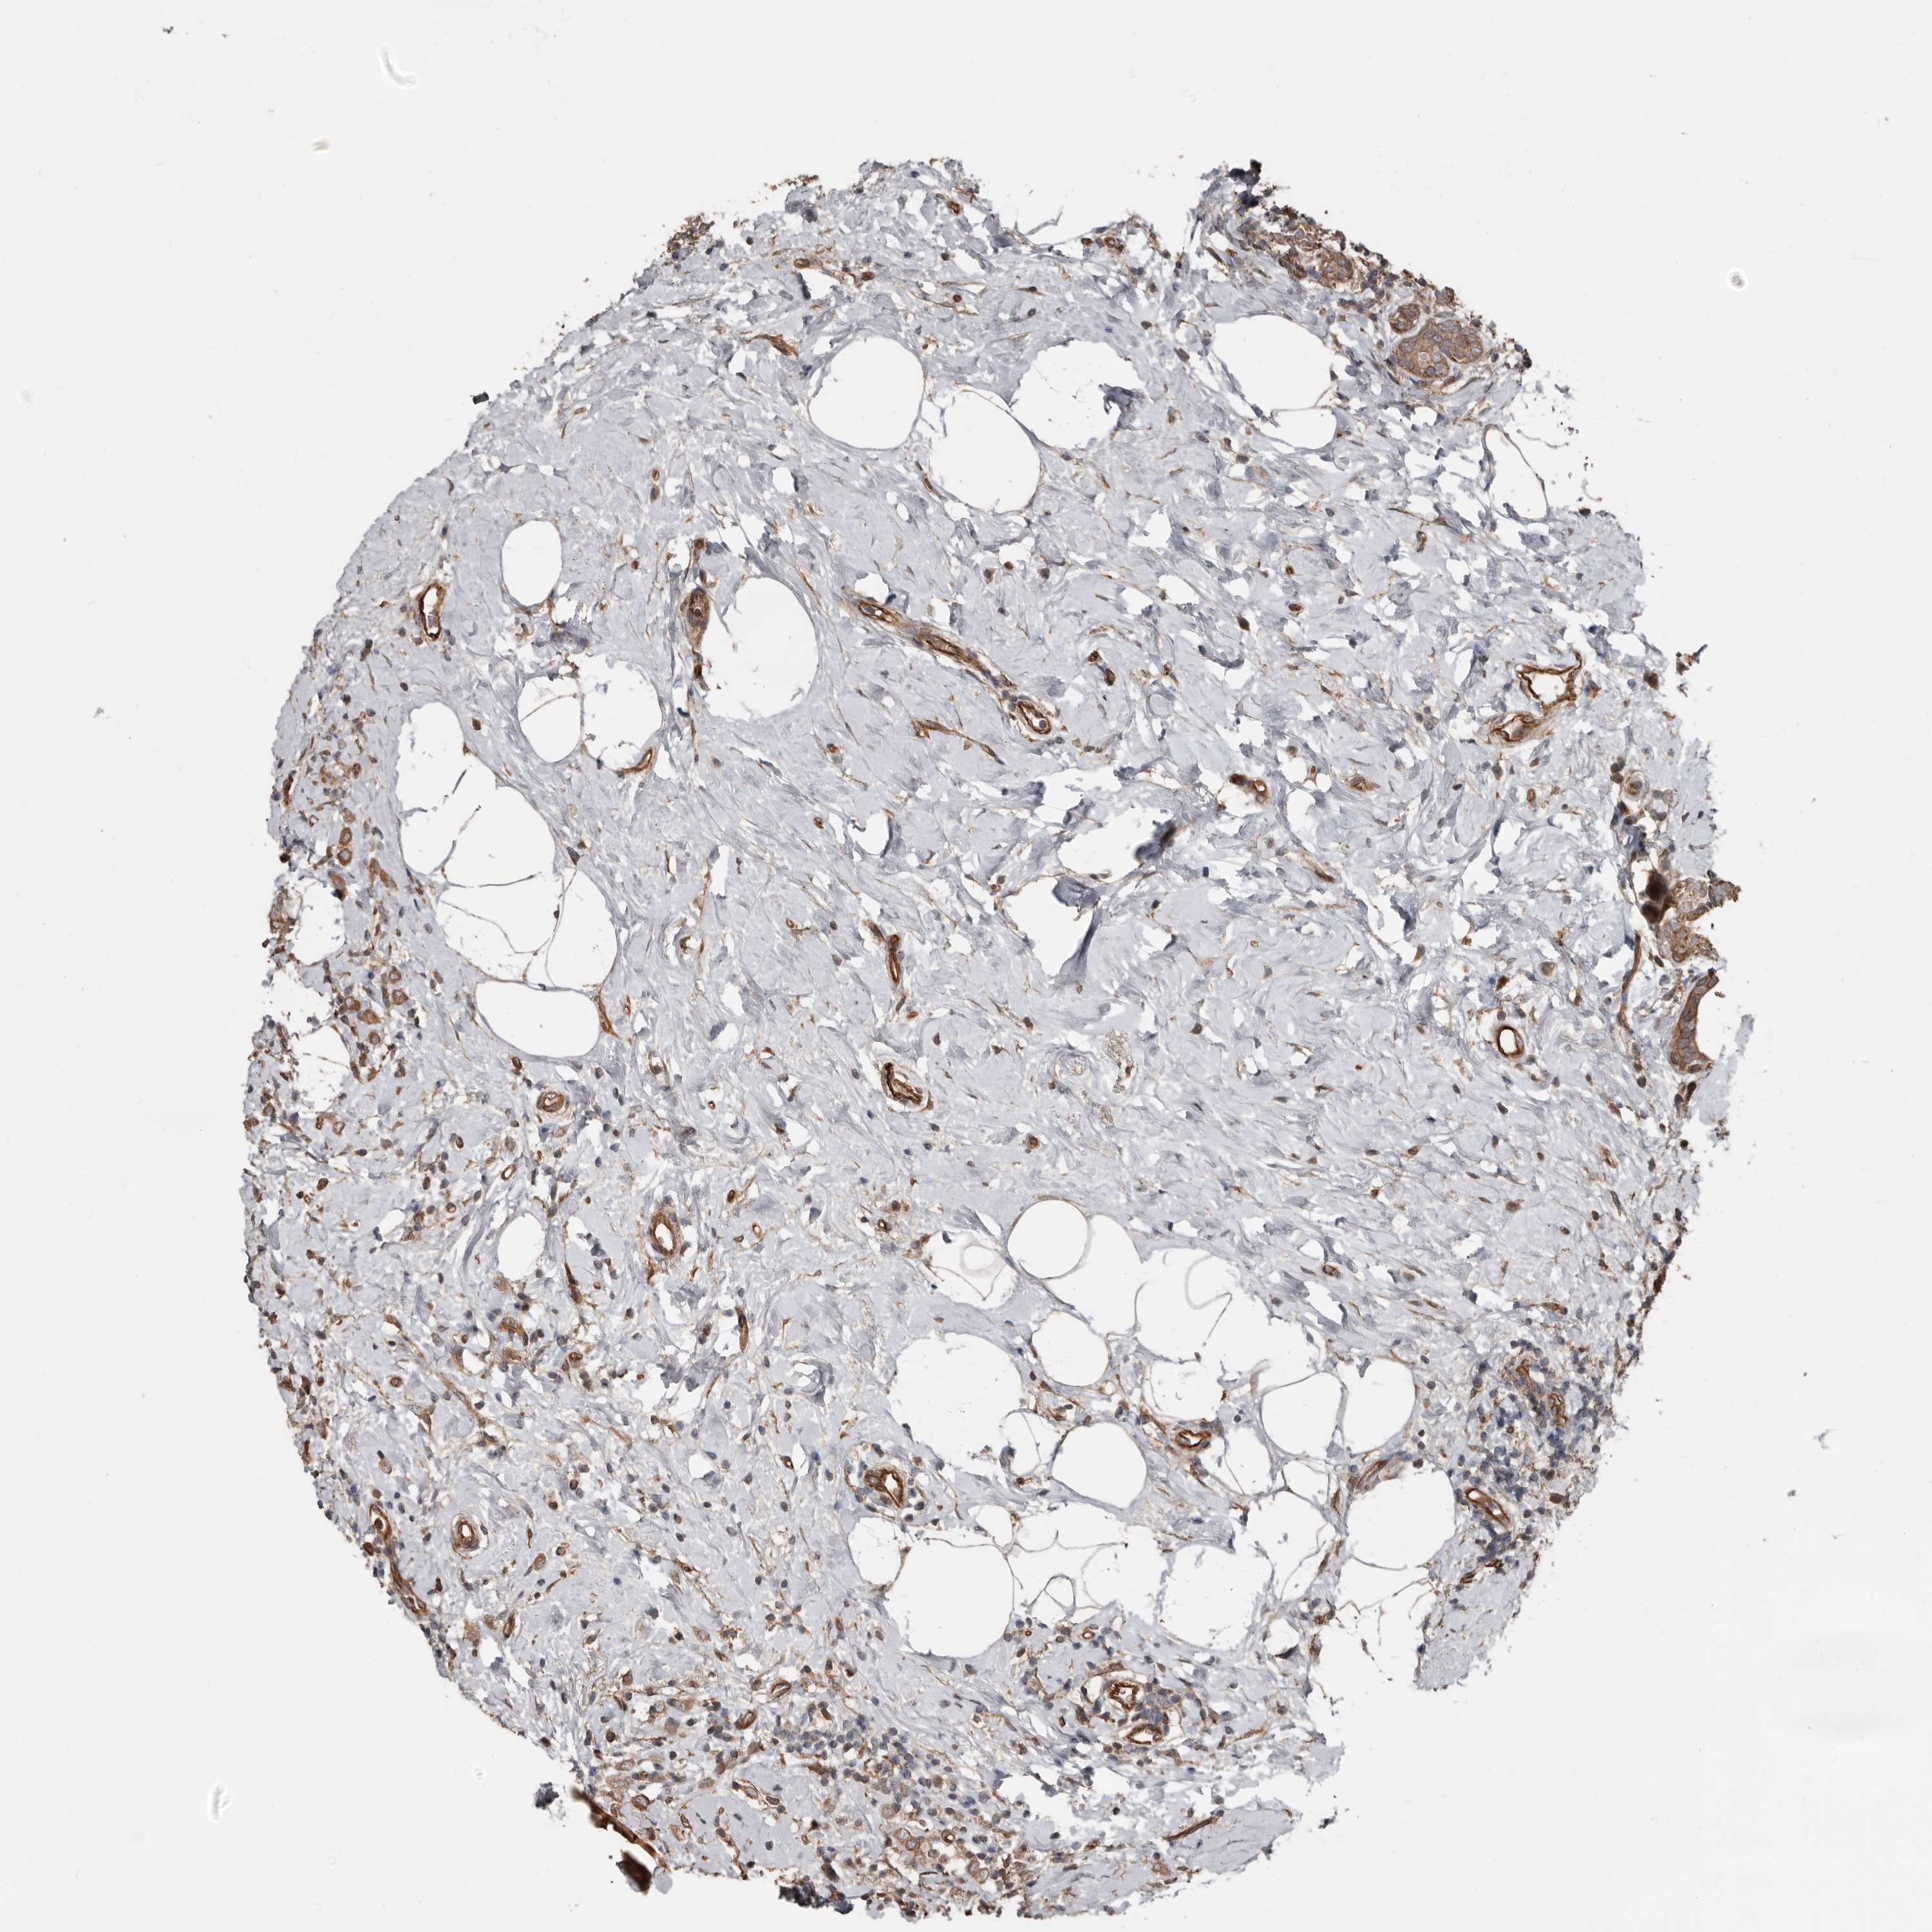

CANCER BREAST CANCER Show tissue menu

BRCA TCGA BRCA VALIDATION PROTEIN EXPRESSION